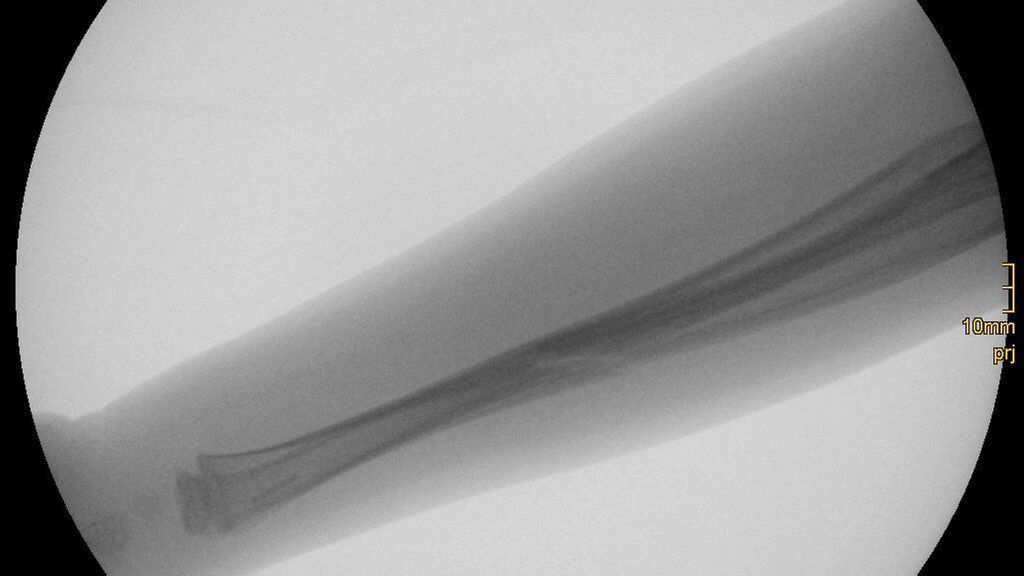

Die in den Studien von Sinikumpu und Korhonen verwendeten Markdrähte aus PLGA wurden von der finnischen Firma Bioretec Oy CE-zertifiziert und unter dem Namen Activa IM-Nail vermarktet, in Österreich vertreibt die Fa. Hofer diese Implantate. In einer europaweiten Multicenterstudie mit aktuell 9 beteiligten Kliniken unter der Leitung der Donau-Universität Krems wird dieses Implantat an einer großen Studienpopulation (>200) evaluiert. Es werden Patienten im Alter zwischen 3 und 13 Jahren mit Unterarmschaftfrakturen nach Einwilligung aufgenommen. Die Einschlusskriterien und damit die Indikation zur operativen Stabilisierung entsprechen der Indikation der bisher verwendeten Titanmarkdrähte. Ein Ziel der Studie ist es, die Anzahl der Refrakturen zu erheben. In der Literatur wird bei konventionell behandelten pädiatrischen Unterarmfrakturen eine Refrakturrate zwischen 1,1% und 16,7% angegeben.38–42 In Österreich startete die Studie im März 2021 im Krankenhaus Mödling. Bisher konnten 6 Patienten in Mödling eingeschlossen werden, europaweit sind 24 Patienten im Rahmen dieser Studie bis jetzt operiert worden. Abgesehen von der Resorption des Materials ist der größte Unterschied des PLGA-Implantats zum bisher üblichen Titanmarkdraht die deutlich geringere Stabilität des Polymers. Aufgrund dessen muss bei der Implantation zunächst ein konventioneller Stahl- oder Titandraht als Dilatator in den Markraum eingebracht werden, der in einem zweiten Schritt durch das PLGA-Implantat ersetzt wird (Abb. 1). Eine postoperative Gipsruhigstellung ist notwendig. Alle Patienten waren bei der Kontrolle nach 2 Wochen schmerzfrei. Die postoperative Gipsruhigstellung ist für die Studienteilnehmer ein geringerer Nachteil als eine zweite Operation zur Metallentfernung, welche bei der konventionellen Operationsmethode notwendig wäre.

Abb. 1: Frakturversorgung mit Activa IM-Nail: a, b) Verletzung; c, d) intraoperativ Fraktur reponiert, Dilatatoren eingebracht; e, f) intraoperativ mit liegenden Implantaten; g, h) Röntgenkontrolle nach 25 Tagen